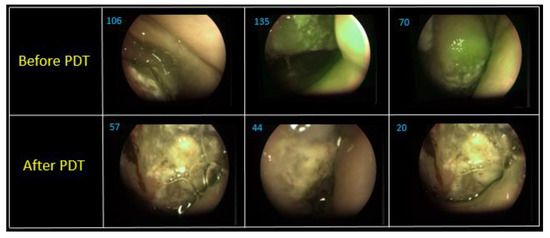

Figure 13 shows combined images of the surface of the tongue back in three different areas. The value of the fluorescence index decreased 1.9–3.5 times in different parts of the lateral tongue surface after PDT. The images show photobleaching of Ce6, which indicates positive tumor cell destruction. A hemiglossectomy was performed 6 days after PDT. Also, a histological research revealed therapeutic pathomorphism of the first degree. The repeated FD and PDT were performed in a month after the first one (Figure 14).

The FD before the second PDT session showed less fluorescence signal in comparison with the fluorescence signal obtained before surgery resection. PDT was conducted with 100 J/cm2 fluence. The FD showed an almost complete photobleaching of the PS in the tumor. Indeed, we noted a 6 times location for the reason that the decrease of the Ce6 fluorescent signal. Today, no data about relapse have been obtained under dynamic observation.

Figure 14. The combined images of mucous and tongue surface before and after PDT.